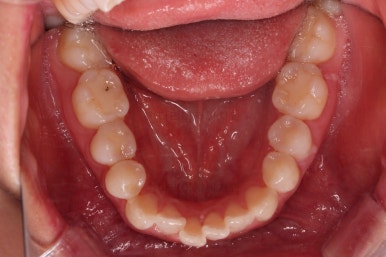

부산교정잘하는치과 초진 시 입안의 모습입ㄴ디ㅏ.

맞물림은 크게 나쁜 편은 아니었고요.

앞니 쪽이 위아래가 다 삐뚤고, 위에 작은 앞니 하나가 거꾸로 물리는 상태였습니다.

거꾸로 물리는 상황에서 특히 아래 앞니는 점점 잇몸이 꺼지는 증상이 생기면서 장기적인 치아의 수명에 영향을 주게 됩니다.